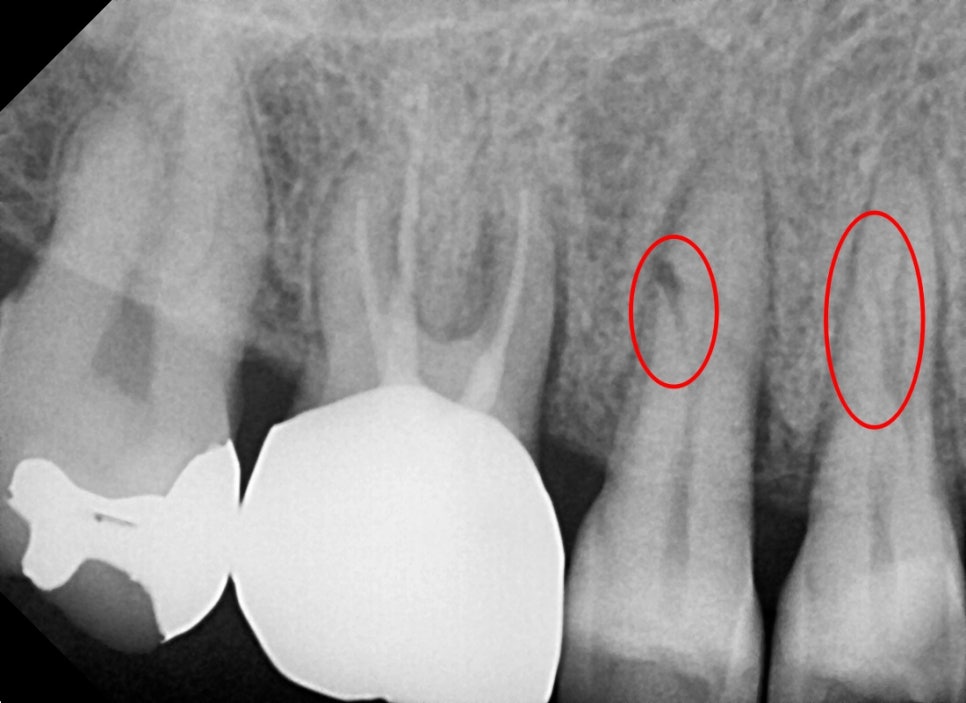

화살표를 보면 검은 선이 보이는데 뿌리에 금이 가서 엑스레이상에도 선명히 보였습니다.

자세한 작은 사진에서는 더 선명하게 보였으며

엑스레이에서 치아의 금간부분이 보인다는 것은

발치를 해야 하는 상황까지 왔다는 것입니다.

아픈지 얼마 안 됐는데 치료로 금간것을 해결할 순 없나요??

안타깝게도 뿌리까지 금이 진행되어 통증이 확인되는 치아는

치아의 머리 부분만 씌워주는 크라운치료를 해도 통증이 없어지는 것은 아니기 때문에

발치가 유일한 치료방법입니다....